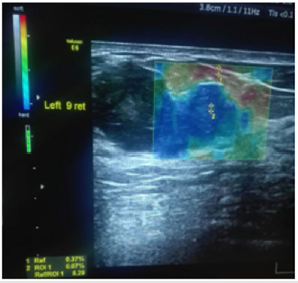

In this study: Fibroadenoma, simple cyst, and fibrocystic changes were the foremost common benign lesions whereas infiltrative ductal carcinoma was the foremost common malignant lesion. Fibroadenomas showed up smooth oval or adjusted in shape with well-defined edges, homogenous echotexture, isoechoic with bilateral acoustic shadowing, wider than taller and either softer than or had the same elasticity as adjoining glandular tissue with score 1, 2 or 3 (Figure 1). Fibroadenomas sometimes have size and stiffness pattern by elastography which is similar to that of malignant lesions as in calcified fibroadenomas with elasticity score 3 or 4 (Figure 2). Malignant breast lesions are speculated, irregularly formed, unwell outlined, with heterogeneous echotexture, distorted design, central shadowing, taller than wider, small calcifications, elastography score 4 or 5. They appeared larger on the elastography image due to higher visualization of the encircling desmoplastic reaction (Figures 3 & 4).

Figure 4: 33 years female with a palpable right breast lump, US and elastography, showed mass dense glandular tissue with score 5 (the lesion was blue color). The final identification was confirmed by core biopsy as ductal carcinoma in situ.